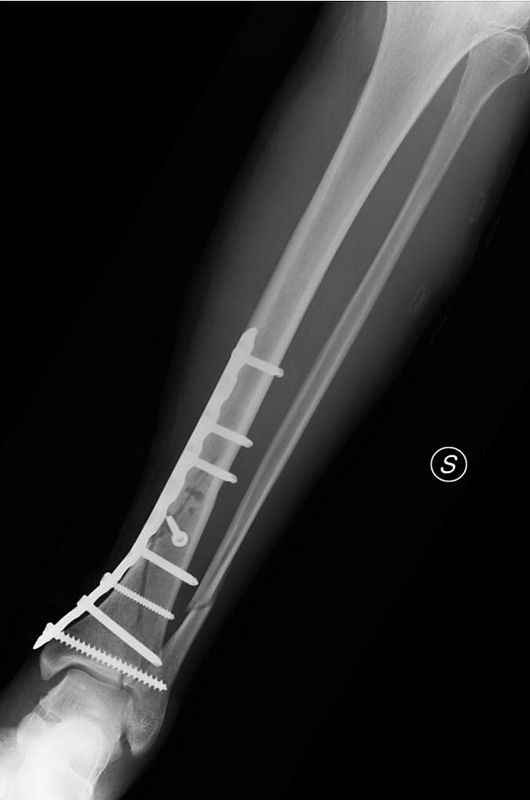

mariusz-w napisał(a):Posiadam także zdjęcia nie rentgenowskie, a wykonane aparatem w telefonie , ale tymi nie będę Was straszył.

longtom napisał(a): A swoją drogą jak skręcam jakieś deseczki albo inne beleczki to wkręty z drugiej strony mi nie wystają.

Ale z kościami widocznie inaczej się robi.